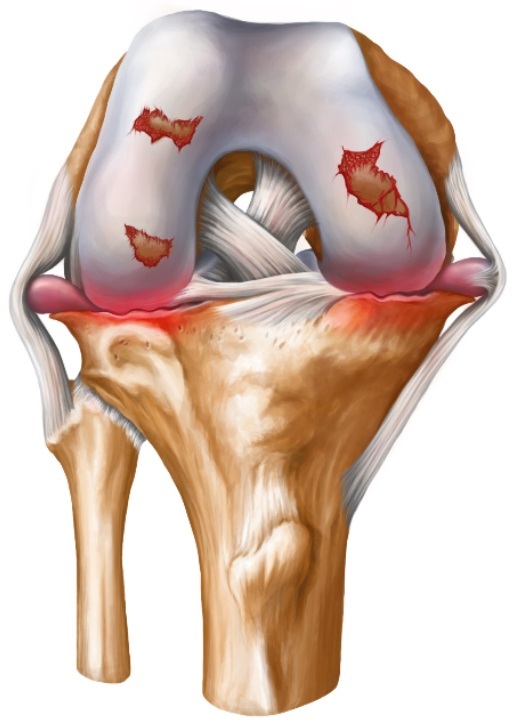

무릎연골화증이란 뼈를 덮고 있는 딱딱해야 할 연골이 노화 및 외상에 의해 수분이 빠져 연골이 말랑하게 연화되는 질환입니다.

무릎 전체 질환을 놓고 봤을 땐 아주 초기 질환에 해당되지만 별병 연령이 낮고 또 방치할 경우 언제든지 퇴행성 질환으로 이어질 수 있어 빠른 진단과 치료가 중요합니다.

한 번 손상된 관절 연골은 회복하기 어려우며, 연골손상이 많이 진행 된 경우에는 어쩔 수 없이 수술적 치료를 하며 초기증상의 경우 운동치료와 약물치료 등 보존적 치료를 통해 증상을 개선할 수 있습니다.